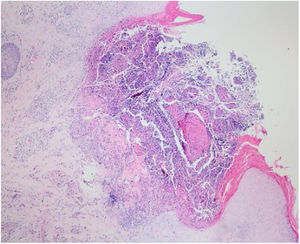

Laboratory results of complete hemogram, blood sugar, liver, and kidney function tests were found to be within normal limits. Histopathological evaluation of a representative skin lesion taken from the left leg showed acanthosis, basket weave orthokeratosis, increased number of vessels in the superficial dermis, and perivascular and interstitial inflammatory infiltrate with erythrocyte extravasation. Punched-out ulceration with cellular debris was observed in the crateriform invagination and transepidermal elimination of collagen fibers (Figs. 4 and 5). ARPC was diagnosed based on the clinical and histological findings and the onset of the disease at the age of 75 years. Treatment with oral acitretin 25mg/day was planned; however, the patient was lost to follow-up. Later, during a control visit to our clinic, an excellent response to gabapentin 300mg/day and topical doxepin cream for one month was observed in the patient; these medications were prescribed in another medical center. Meanwhile, a diagnosis of prostate adenocarcinoma was confirmed following prostate biopsy due to elevated serum levels of prostate-specific antigen.